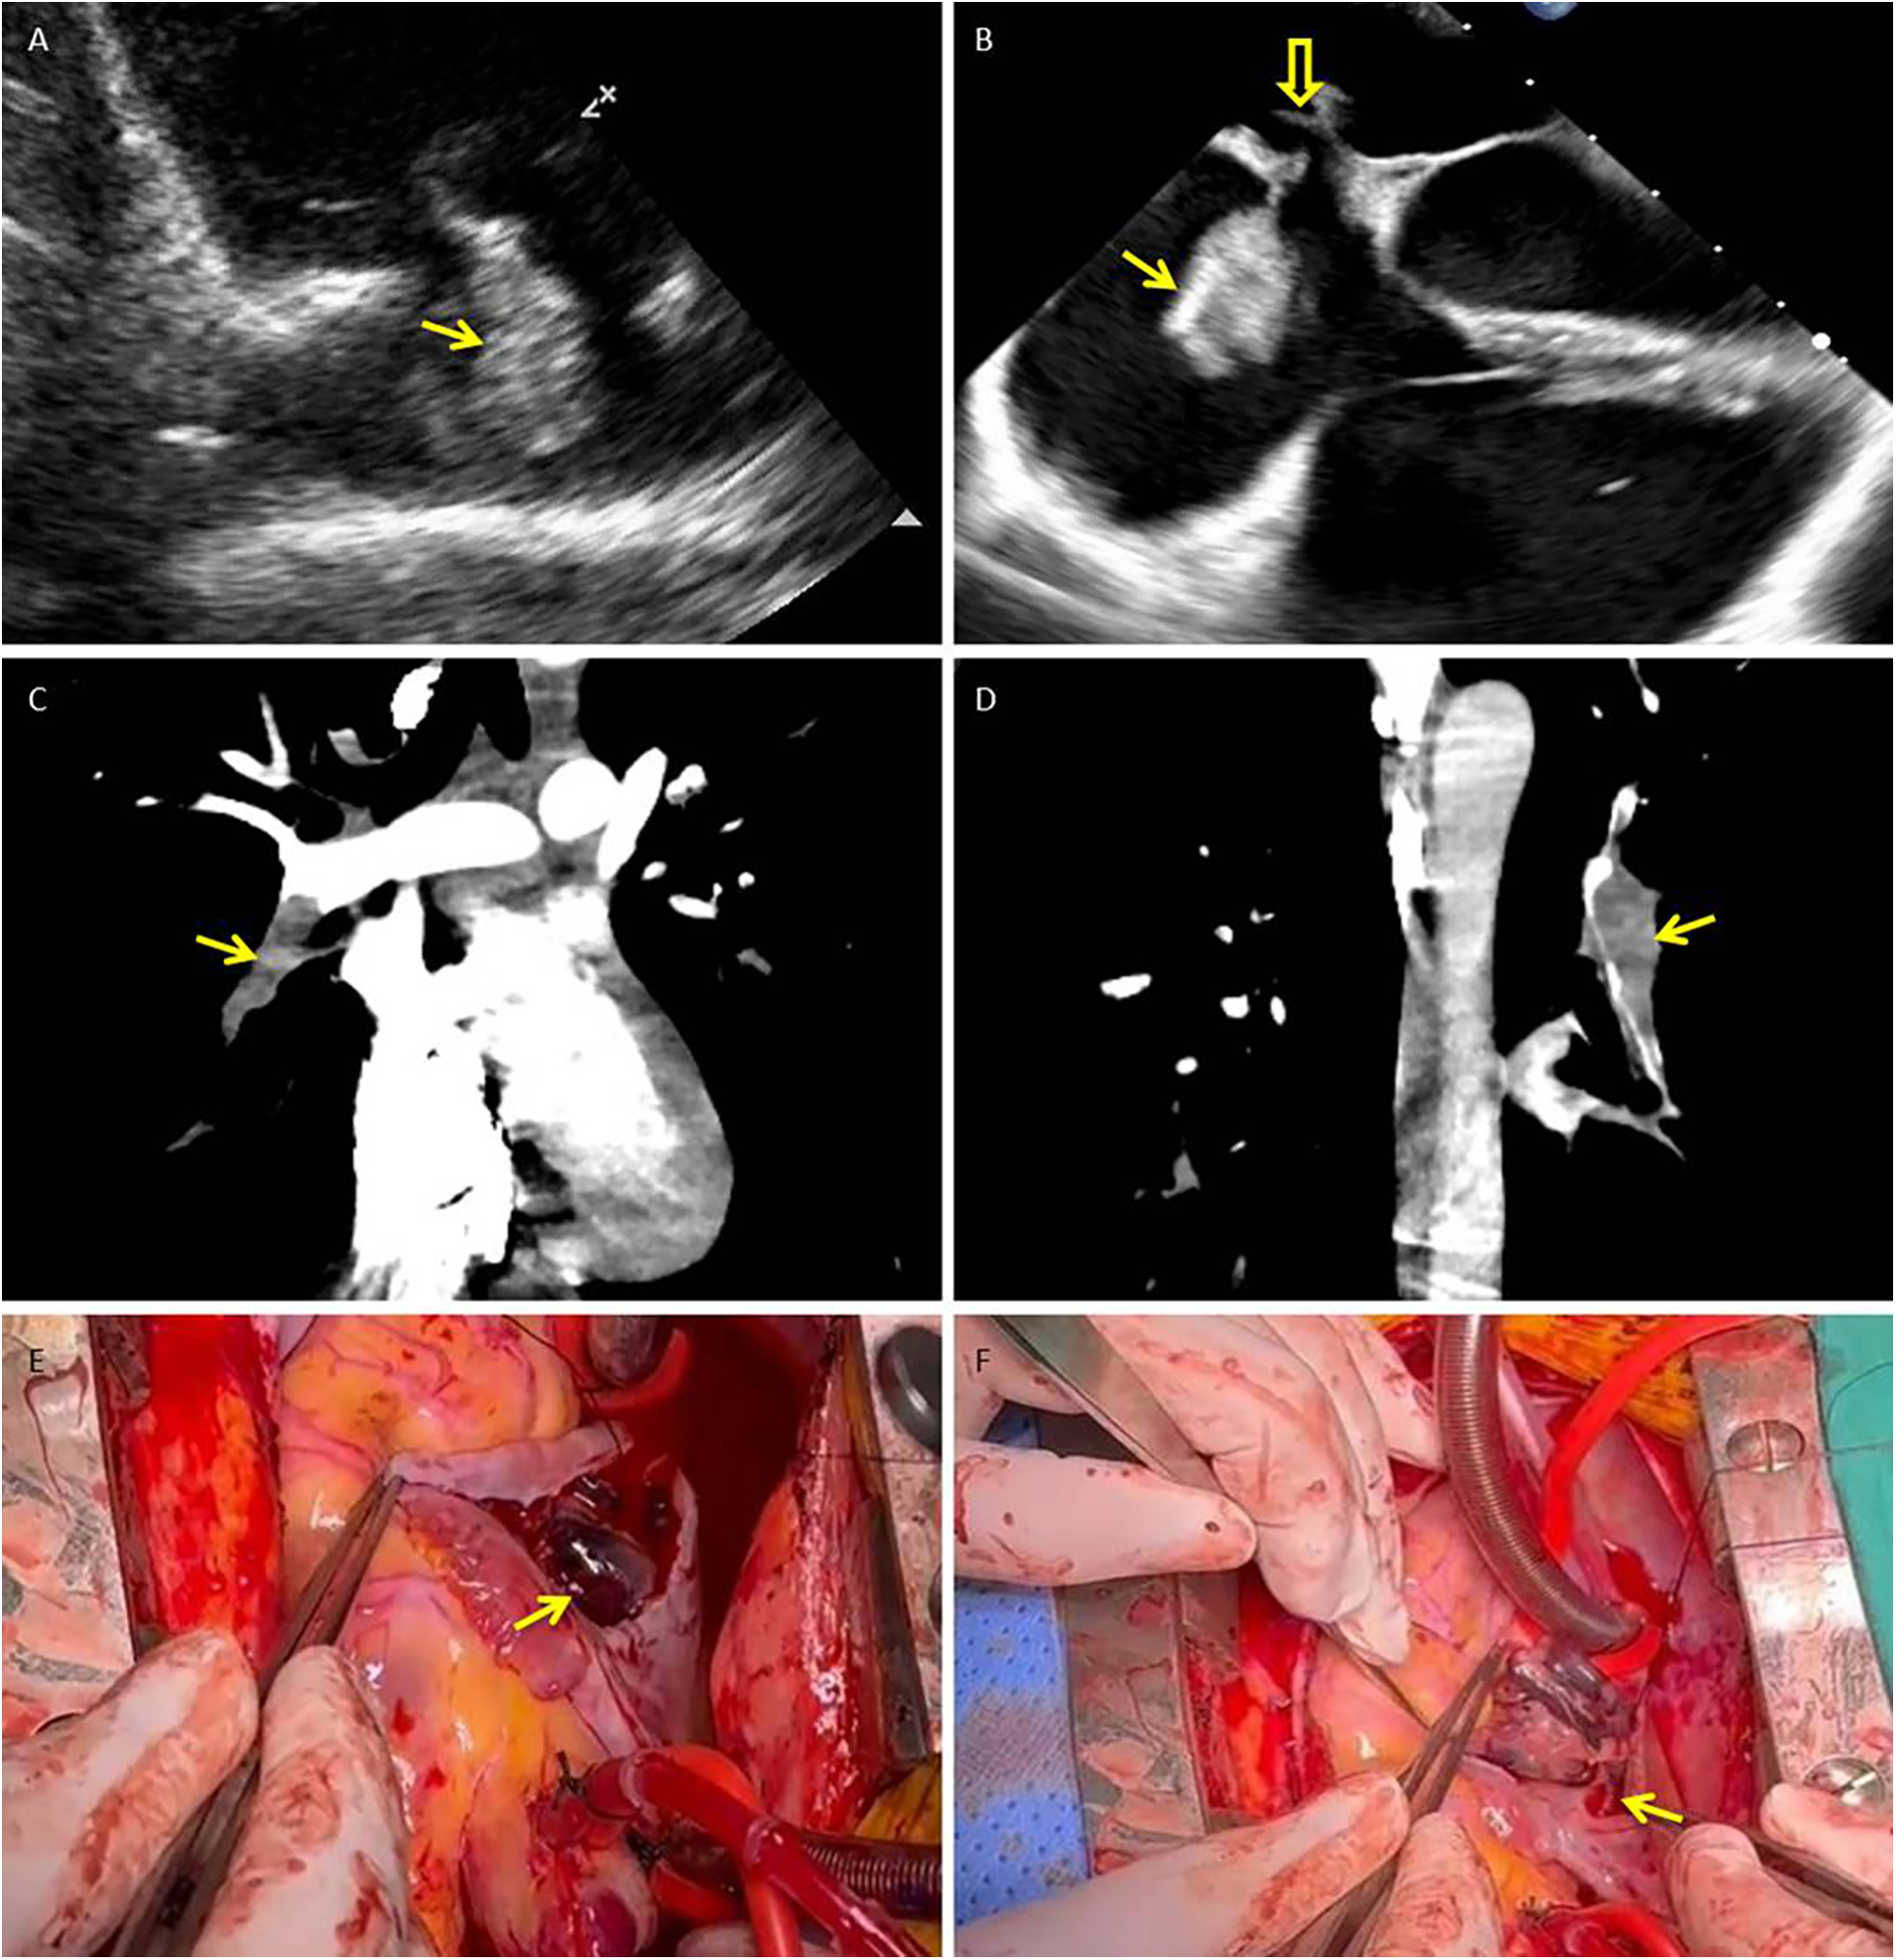

A 21-year-old man with sudden-onset severe dyspnea, profuse sweating, and transient loss of consciousness presented at our emergency department in May 2025. The day before symptom onset, he had undergone a long-distance train journey with prolonged immobilization. His medical history included a right lower leg fracture treated with internal fixation in 2020 and cerebral infarction secondary to cerebral venous thrombosis in 2023. After recovery from cerebral venous thrombosis, he was prescribed oral rivaroxaban (15 mg once daily) for secondary prevention but self-discontinued this medication approximately one year before admission, without medical advice. On admission, laboratory tests revealed markedly elevated levels of D-dimer (50.43 mg/L FEU; reference 0.00–0.50) and fibrinogen degradation products (>124.00 mg/L; reference 0.00–5.00). His oxygen saturation was 85% on room air. Transthoracic echocardiography (TTE) revealed a highly mobile, serpiginous mass within the right atrium (RA) consistent with a thrombus in transit, measuring approximately 35 × 22 mm (Figure 1A). Transesophageal echocardiography (TEE) revealed a moderately echogenic thrombus straddling the patent foramen ovale (PFO) and prolapsing into the left atrium (LA), accompanied by right-heart enlargement and pulmonary hypertension (Figure 1B). CT pulmonary angiography (CTPA) confirmed extensive bilateral pulmonary embolism (Figures 1C,D). Cerebral angiography revealed a patent intracranial arterial tree without hemorrhage or new embolic occlusion. Preoperative bilateral lower extremity venous Doppler ultrasonography did not reveal residual deep vein thrombosis.

Figure 1

Thrombus in transit straddling a patent foramen ovale with concurrent pulmonary embolism: multimodality documentation and operative retrieval. (A) Transthoracic echocardiography (right ventricular inflow view) shows a highly mobile, serpiginous thrombus within the right atrium (arrow). (B) Transesophageal echocardiography (mid-esophageal four-chamber view) demonstrates the thrombus straddling the PFO (solid arrow), with its distal segment prolapsing into the left atrium (hollow arrow); right-sided chamber enlargement is present. (C,D) CT pulmonary angiography (coronal reformations) reveals acute pulmonary emboli, including an intraluminal filling defect in the right lower-lobe pulmonary artery (C) and additional defects in distal branches of the left pulmonary artery (D) (arrows). (E,F) Intraoperative photographs: (E) shows the large, friable thrombus (measuring approximately 2.0 × 8.5 cm) immediately after the right atrium was opened (arrow). (F) demonstrates the narrow stalk (approximately 3 mm) of the thrombus arising from the PFO ostium (arrow). PFO, patent foramen ovale; RA, right atrium; LA, left atrium; RV, right ventricle; TTE, transthoracic echocardiography; TEE, transesophageal echocardiography; CTPA, CT pulmonary angiography.

The patient underwent emergency surgery. Through a right atriotomy, a friable thrombus measuring approximately 2.0 × 8.5 cm was removed from the RA; a narrow stalk (∼3 mm) appeared to originate from the PFO ostium (Figures 1E,F). Additional dark thrombi were evacuated from the LA and the left upper, lower, right middle, and lower pulmonary arteries. Surgical closure of the PFO was performed, and a temporary inferior vena cava (IVC) filter was implanted at the end of the procedure as a prophylactic measure to reduce the risk of early recurrent embolism during the perioperative period, when full-dose anticoagulation needed to be carefully re-introduced. Postoperatively, low molecular weight heparin was started on postoperative day 1, followed by a transition to warfarin with an overlap period. Warfarin was continued until hospital discharge, after which long-term secondary prevention was maintained with rivaroxaban once daily. Histopathological examination confirmed organized thrombi in the RA, LA, and pulmonary arterial specimens. Follow-up TTE on postoperative days 15 and 29 revealed no residual intracardiac thrombus and no echocardiographic evidence of right heart strain. Subsequently, a targeted next-generation sequencing panel for hereditary cerebrovascular disease identified a heterozygous nonsense variant in SERPINC1 (c.51T > A, p.Tyr17*), classified as likely pathogenic for antithrombin III deficiency, together with missense variants in PROC (c.629C > T, p.Pro210Leu) and MTHFR (c.665C > T, p.Ala222Val; c.136C > T, p.Arg46Trp; c.700G > A, p.Asp234Asn). According to the laboratory report, only the SERPINC1 variant was considered likely pathogenic, whereas the other variants were of uncertain or modest clinical significance.

In Case 1, TTE and TEE demonstrated a large, highly mobile serpiginous thrombus within the RA that straddled the PFO and prolapsed into the LA, accompanied by right heart enlargement and pulmonary hypertension—typical features of an embolus in transit. Migratory PFO thrombi are usually elongated, with few attachment points and marked excursion; they can be seen drifting between the atria during the cardiac cycle (6–8). They often occur in younger or middle-aged patients who present abruptly with chest pain, dyspnea, hypoxemia, syncope, or shock in the context of acute venous thromboembolism (9, 10). Our patient had a history of right lower leg fracture and prior cerebral venous thrombosis with ischemic stroke, had recently undergone a long-distance train journey with prolonged immobilization, and presented with massive pulmonary embolism on CTPA. Although preoperative ultrasound did not reveal residual DVT, the combination of a large free-floating RA thrombus straddling the PFO, massive pulmonary embolism, and this thrombotic history strongly supported the diagnosis of an embolus in transit originating from the peripheral venous system. His subsequent genetic testing demonstrated a likely pathogenic SERPINC1 nonsense variant (antithrombin III deficiency), further suggesting that this extreme presentation occurred on a background of hereditary thrombophilia and venous thromboembolism susceptibility. In this context, emergency surgical removal of thrombi from the RA, PFO, and pulmonary arteries, combined with PFO closure and temporary IVC filter placement, was considered the most appropriate strategy to prevent further embolization.